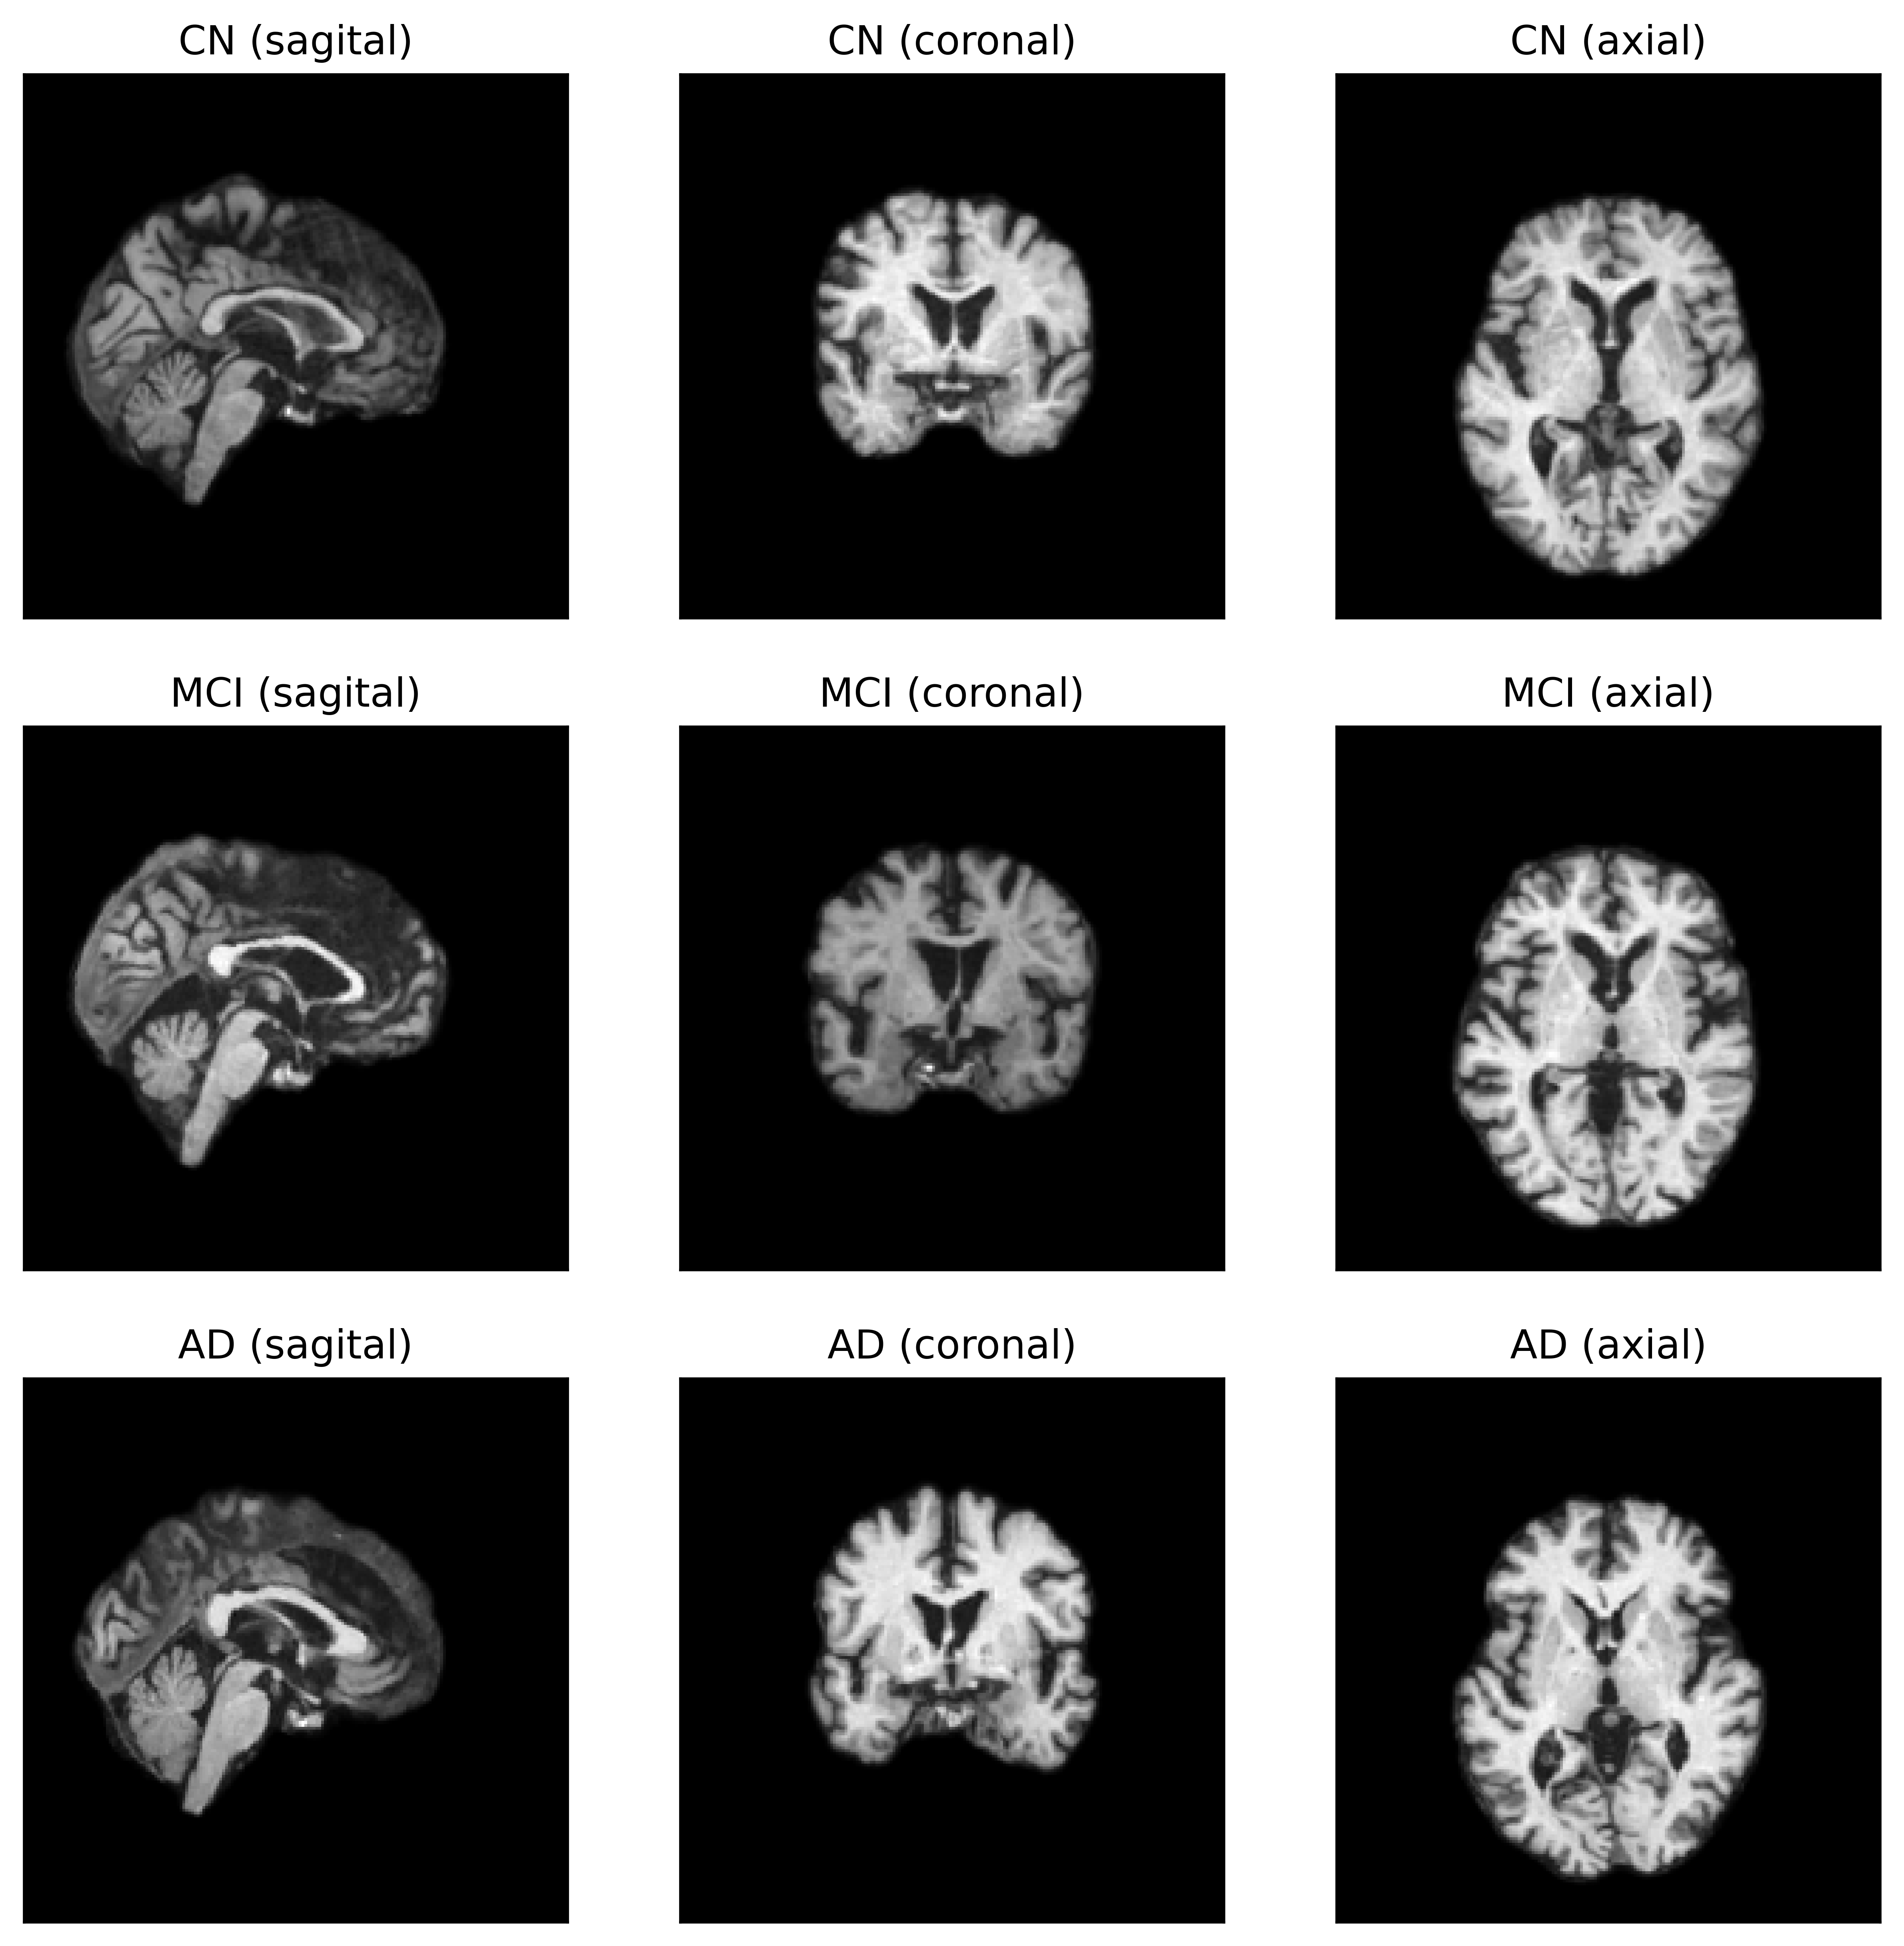

Refer to caption

Figure 2: Sagital, coronal and axial view of a sample image from each class of ADNI dataset